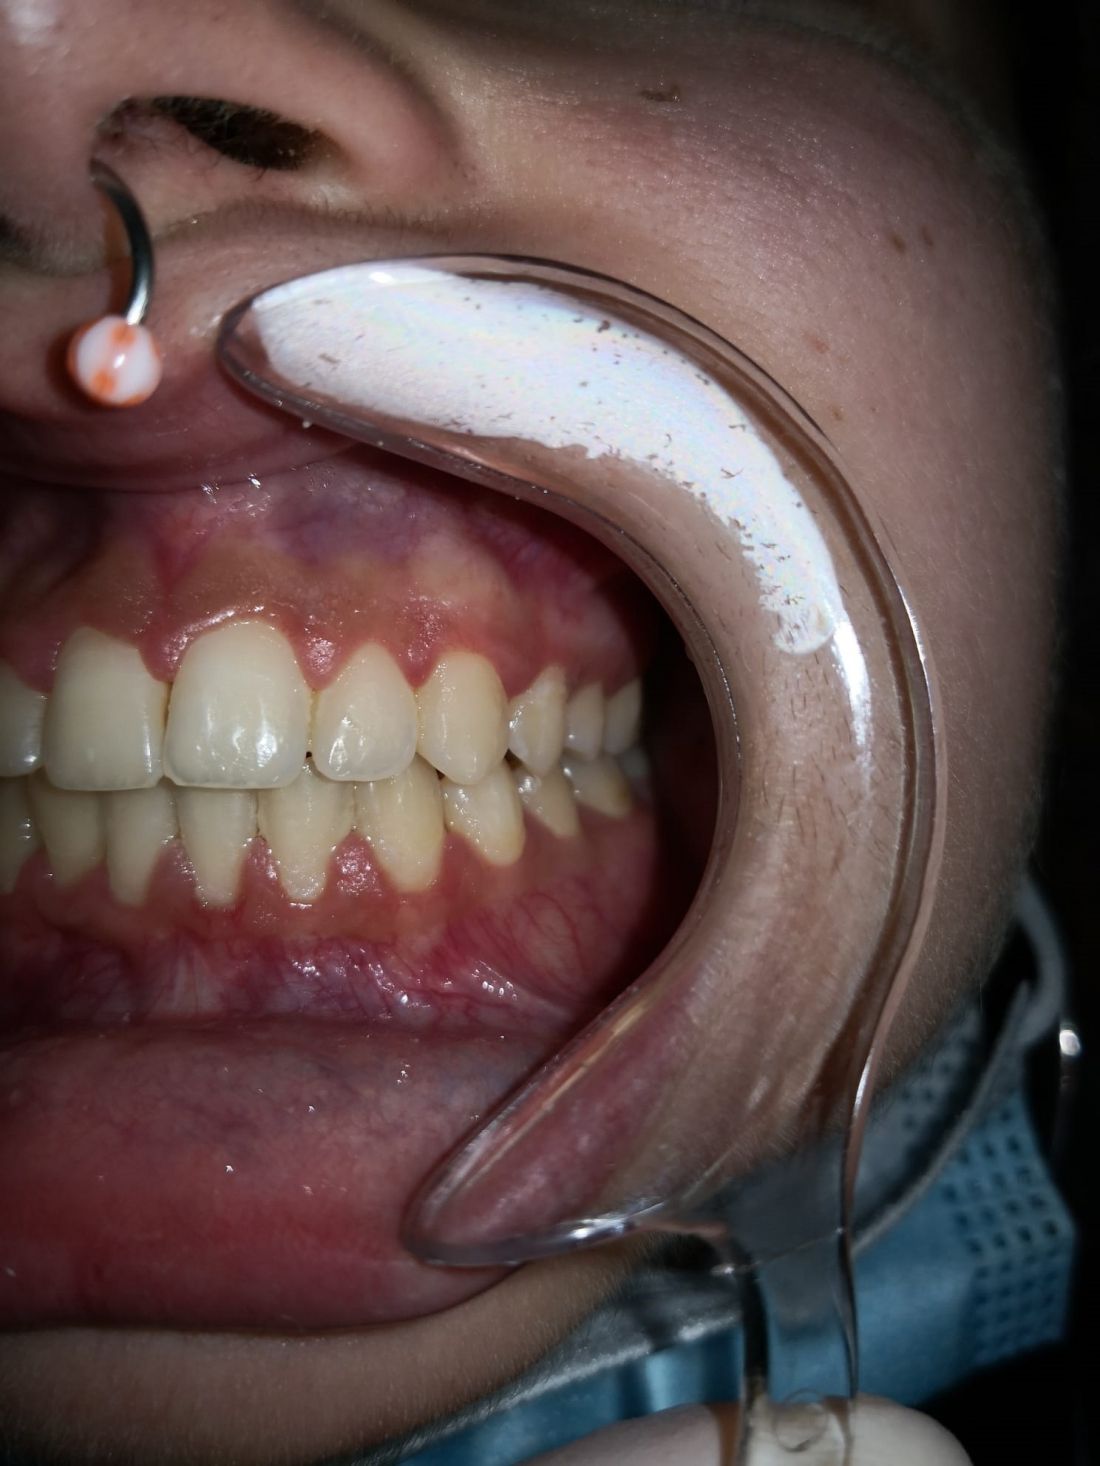

Ortopedia ortodoncia transposición